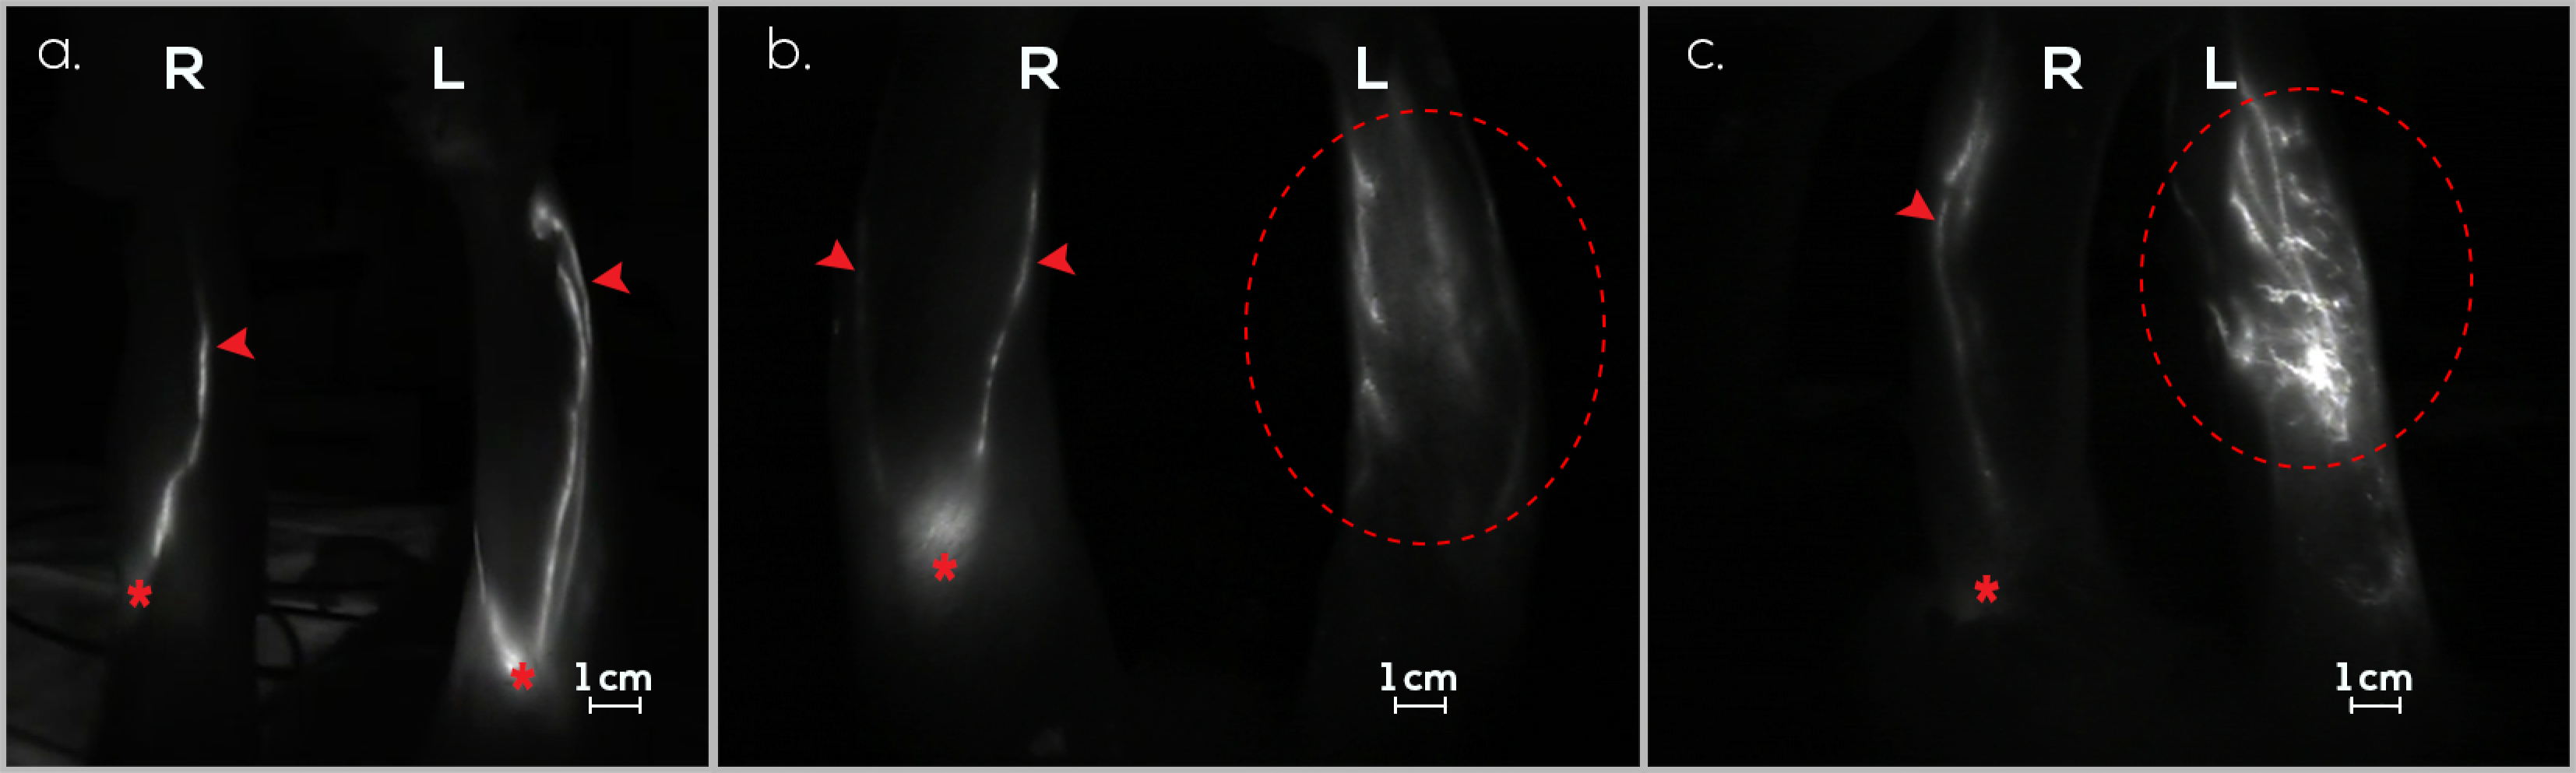

3.1. Treatment Group (G1)

3.2. Preventive Group (G2)

3.3. Control Group (G3)

3.4. Follow-Up Assessments